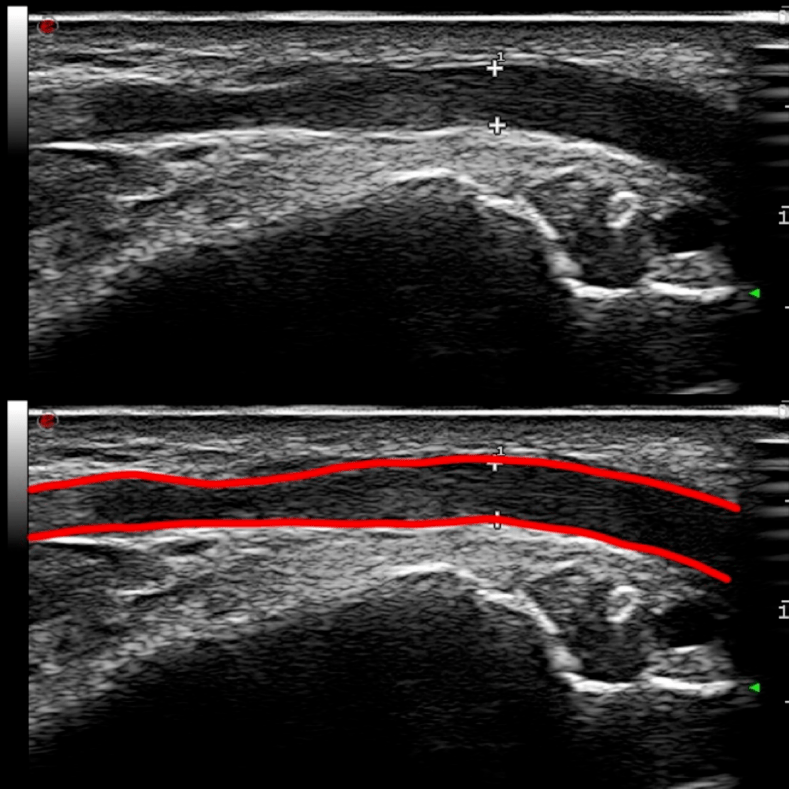

图3

尺神经近端增宽,回声减低,神经束显 示模糊。